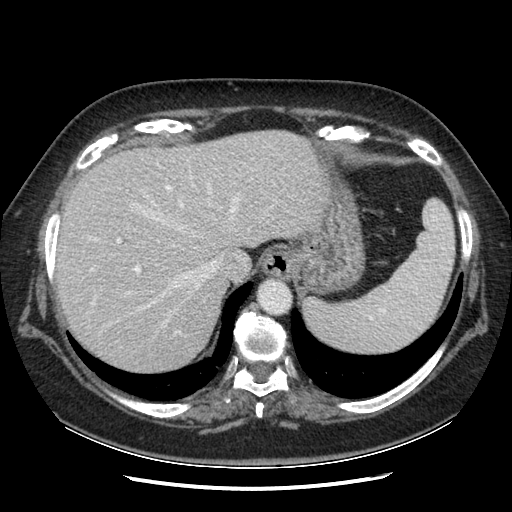

Original NATIVE CT scan (input)

Full window (WL 1023.5, WW 4095 β†’ Low βˆ’1024, High +3071)

Actual HU range: [-160.0, 240.0]